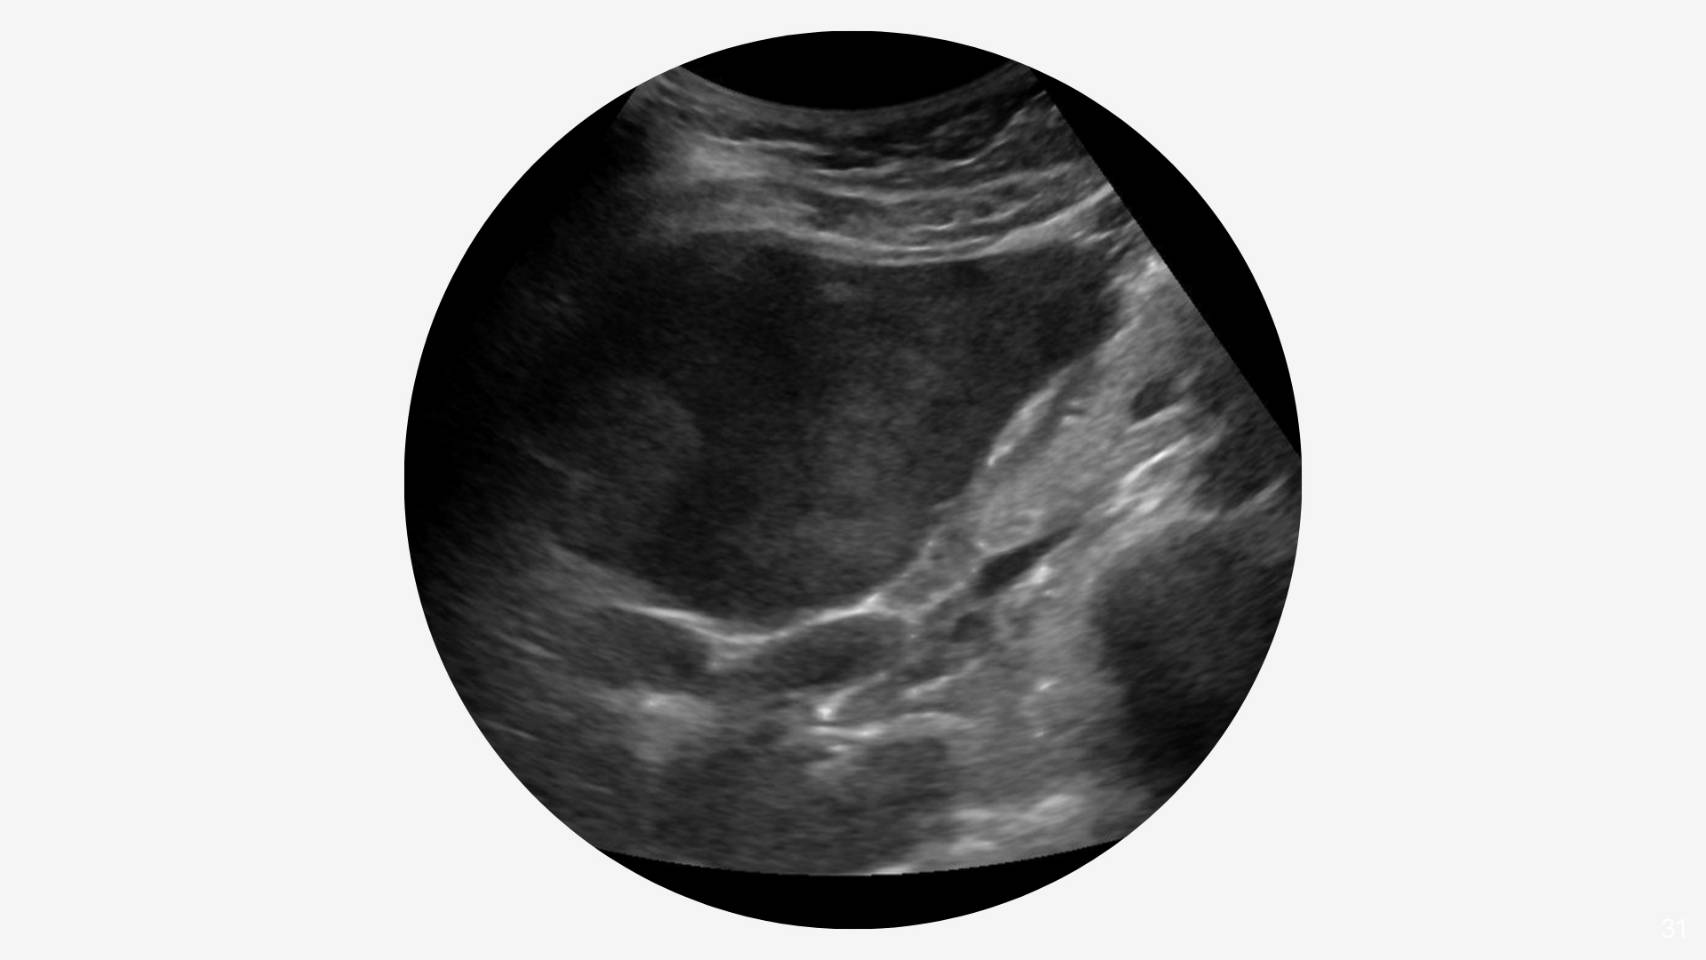

SmartLiva ทำงานเหมือน “อัปเกรด” จากภาพอัลตราซาวด์ขาวดำธรรมดาให้กลายเป็นผลวินิจฉัยที่อ่านง่ายและแม่นยำ โดยแพทย์อัปโหลดภาพผ่านเว็บได้ทั้งบนคอมพิวเตอร์หรือแท็บเล็ต จากนั้นระบบจะช่วยปรับภาพให้ชัดขึ้น คัดเฉพาะบริเวณเนื้อตับที่ต้องวิเคราะห์ และทำให้ภาพดูเข้าใจง่ายขึ้นด้วยการไฮไลต์เป็นสี (เช่น ตับเป็นสีแดง ไขมันเป็นสีเหลือง) เพื่อให้เห็นความผิดปกติได้ทันที โดย AI จะทำการประเมิน 3 เรื่องพร้อมกัน คือ ประเมินระดับพังผืด/ความแข็งของตับ (F0–F4) ตรวจหาความผิดปกติของเนื้อเยื่ออย่างถุงน้ำหรือมะเร็งตับ และตรวจหาพยาธิใบไม้ตับ ซึ่งตัว AI จะทำการประมวล วิเคราะห์ และสรุปผลออกมาเป็นรายงานพร้อมภาพประกอบและคำอธิบายที่คนทั่วไปเข้าใจได้ โดย AI ทั้งหมดถูกฝึกฝน (Train) ด้วยฐานข้อมูลภาพอัลตราซาวด์กว่า 50000 ภาพ จากโรงพยาบาลชั้นนำ อย่างโรงพยาบาลขอนแก่น โรงพยาบาลจุฬาลงกรณ์ และโรงพยาบาลรามาธิบดี